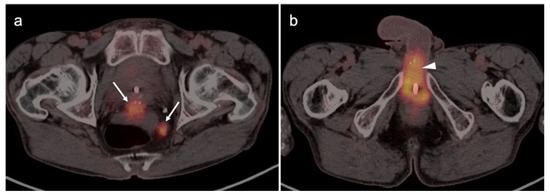

2.6. Vulvar Carcinoma